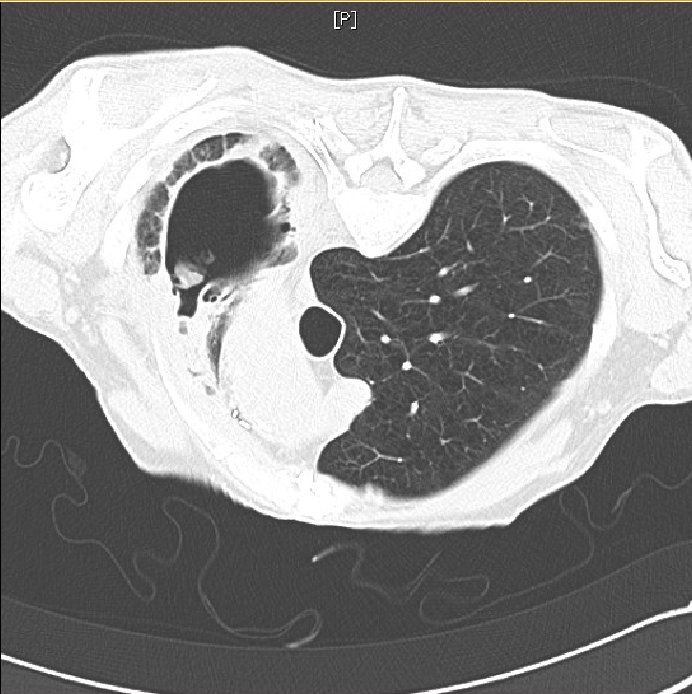

Figure 4. Air-fluid level in apical cavity with adjacent upper-lobe consolidation.

Figure 5. CT Angiography. No pulmonary embolus was identified, a consolidation surrounding the cavity was seen and new “tree-in-bud” opacification was present in the right-lower lobe.

The consolidation surrounding the cavity on CT and the new tree-in-bud opacification are suggestive of pulmonary infection, be it bacterial or fungal. This upper-lobe consolidation is also apparent on the plain chest radiograph, as is an air-fluid level. The above findings would be consistent with bacterial pneumonia, and the presence of an aspergilloma-containing cavity increases the susceptibility to bacterial infection. The clinical picture would also be consistent with a bacterial superinfection – cough productive of green sputum, upper-lobe crackles on auscultation and raised white cell count with associated neutrophilia. Diagnosis would be based on a positive bacterial culture on sputum or bronchoalveolar lavage specimens, and clinical and radiological improvement with appropriate antibiotic treatment.